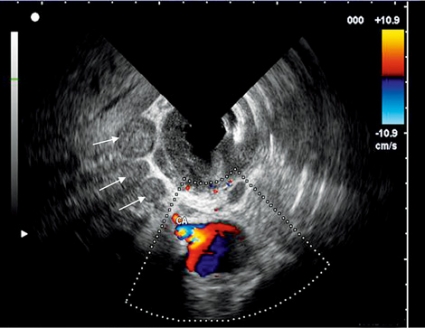

Cancer i gastrointestinalkanalen stadieindelas baserat på TNM-systemet, vilket inkluderar infiltrationsdjupet (T), förekomst av spridning till lokala lymfkörtlar (N) (Figur 5) och förekomst av fjärrmetastaser (M).

Endoskopiskt ultraljud har visat sig vara effektivt vid T- och N-stadieindelning av cancer i gastrointestinalkanalen och är den mest känsliga metoden för regional stadieindelning och resektabilitetsbedömning av cancer i esofagus, ventrikel och rektum. Däremot är endoskopiskt ultraljud inte effektivt för detektion av fjärrmetastaser om de inte är lokaliserade runt mag–tarmkanalen. För värdering av fjärrmetastaser till lunga och lever är datortomografi (DT), magnetkamera (MR) och positronemissionstomografi (PET) mer ändamålsenligt.